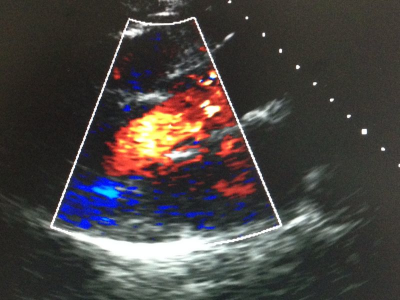

A transoesophageal echocardiogram was performed and documented a mobile endocardial vegetation of 9mm attached to the non-coronary sinus with a massive regurgitating jet leading to severe aortic insufficiency (Figures 3&4). The patient was transferred for emergency heart surgery with extraction of the morphine reservoir previously administered. Severe destruction of the left and right coronary cusps and vegetations on the noncoronary cusp were found. The aortic valve was replaced by a mechanical prosthesis (Carbomedics nr.21). A polymerase chain reaction from the native aortic valve confirmed the presence of bacterial DNA from S. pneumoniae. Following liaison with infectious diseases specialist, she completed an appropriate course of 42days of ceftriaxone plus 28days of vancomicine. With a triad on pneumococcal meningitis, pneumonia and endocarditis, a diagnosis of Austrian syndrome was made. On a follow-up of one year after discharge home, she remained stable with no significant anatomic or functional heart abnormalities.

Figure 3 Transoesophageal echocardiogram documented a mobile endocardial vegetation of 9mm attached to the no coronary sinus.

Figure 4 Transesophageal echocardiogram documented a massive regurgitating jet leading to severe aortic insufficiency.